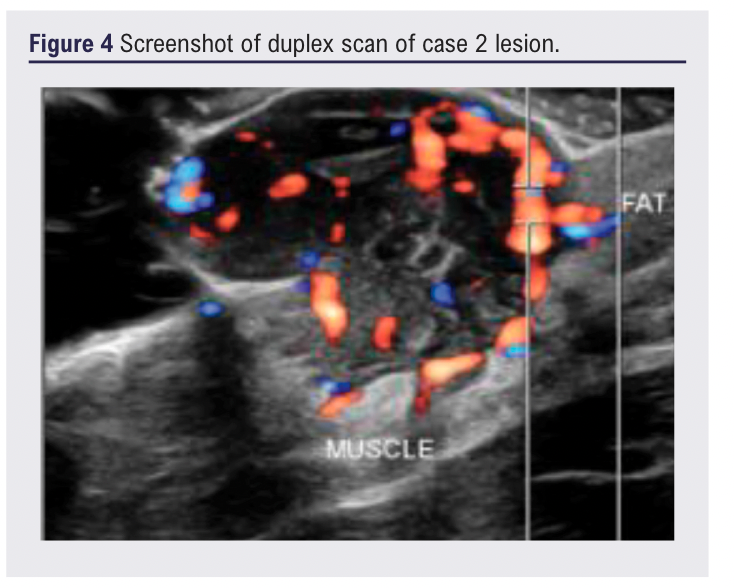

A 35-year-old man presented with a 12-month history of an enlarging blue-tinged nodule on the upper limb, reporting bleeding on contact, but without systemic symptoms (Figure 3). Ultrasound demonstrated an 18×14×15 mm well-defined hypoechoic lesion within the subcutaneous fat, with moderate arterial flow and suspected feeder vessels, reported as having features suggestive of a haemangioma or AVM (Figure 4). Referral to the community dermatology service was redirected to general surgery who, having reviewed the ultrasound report, redirected him to vascular services as a probable AVM.